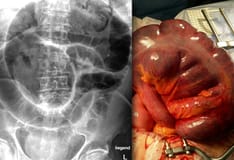

Grossly, surgical specimens are rigid and thickened owing to chronic inflammation and fibrosis during healing periods. The mesentery is typically thickened and foreshortened and may partly surround the bowel wall in a phenomenon known as “creeping fat” (see the image below). The transmural nature of inflammation contributes to possible fistulous connections between segments of bowel or other organs.

Laparoscopic view depicts creeping fat along the mesentery of the terminal ileum.